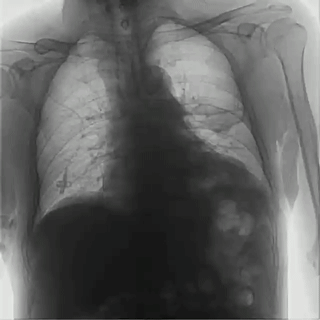

首先,具有可視化操作的功能,能通過(guò)多角度動(dòng)態(tài)影像觀察,瞬時(shí)高清點(diǎn)片,更好地發(fā)現(xiàn)病灶并進(jìn)行相關(guān)疾病的治療,解決了常規(guī)靜態(tài)DR不能解決的問(wèn)題,減少漏診誤診,提高臨床診斷的精準(zhǔn)性。

其次,臨床應(yīng)用更加廣泛,能為影像科提供全科解決方案,針對(duì)體檢科、內(nèi)科、外科、骨科、急診科等也能提供相應(yīng)的解決方案,且檢查更精準(zhǔn)、直觀,擺位攝片效率極大地提升,大大節(jié)省拍片時(shí)間。

而且,影像采集幅面大,17×17英寸超大視野可覆蓋成年人的全胸全腹,并且能在連續(xù)動(dòng)態(tài)中實(shí)時(shí)高清點(diǎn)片,從而達(dá)到精準(zhǔn)診斷的目的。設(shè)備靈活高效的多維度運(yùn)動(dòng)設(shè)計(jì),也帶來(lái)了更加智能化、人性化操作體驗(yàn),可大幅提升檢查效率。